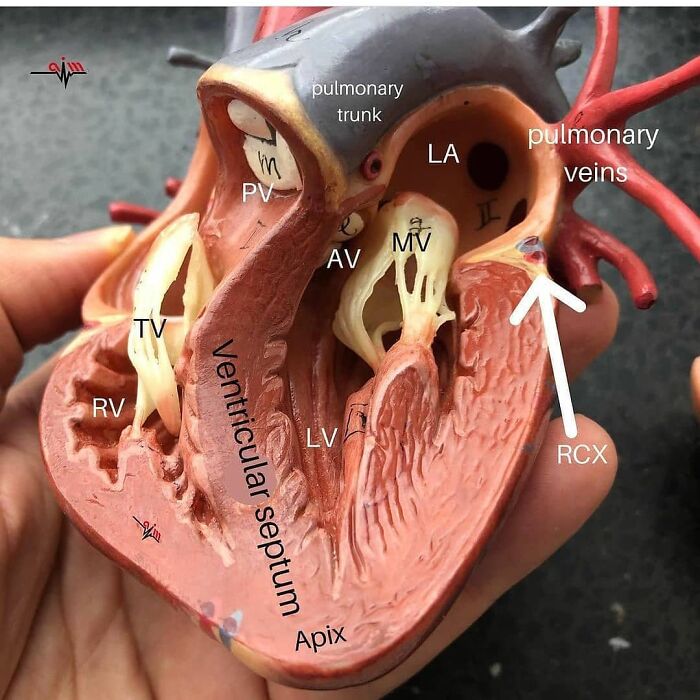

Pediatric Heart Transplantation

Heart Valve